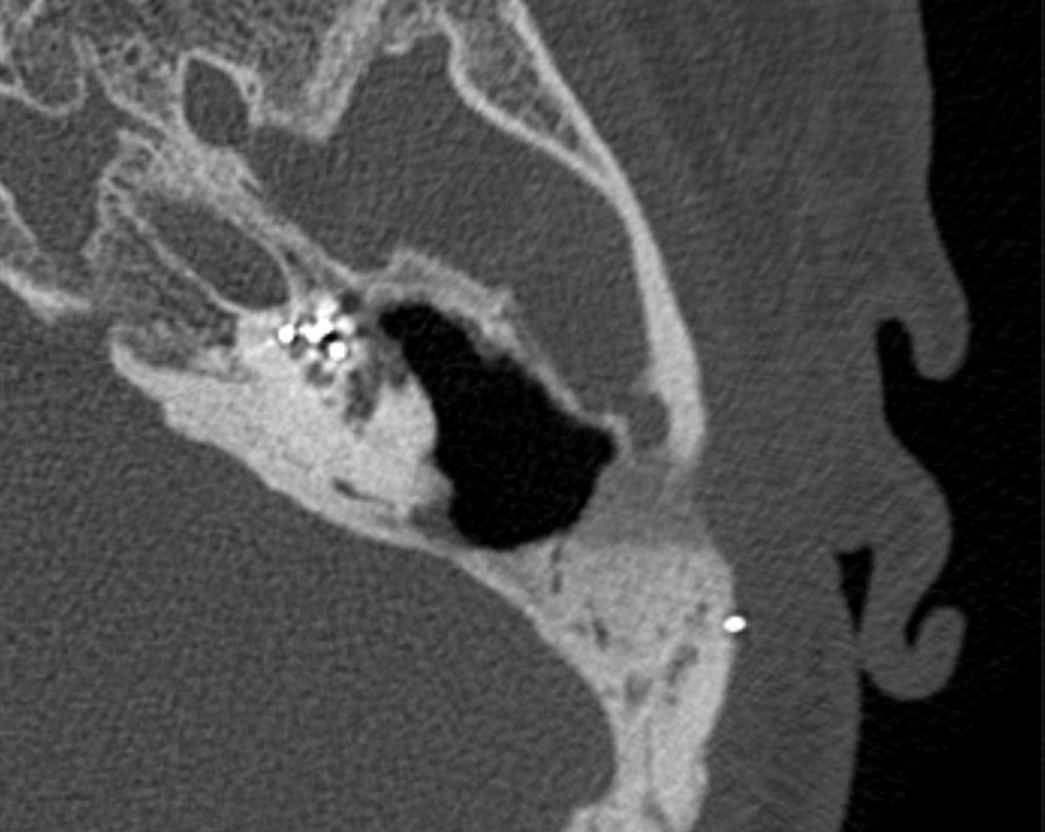

Пациент с эпитимпанитом, у которого в анамнезе была проведена антромастоидотомия на имплантируемом ухе. КИ проводилась одномоментно с ревизией мастоидальной полости. В ходе операции при отсепаровке мягких тканей в антромастоидальной полости визуализировалась холестеатома (рисунки 1, 2).

Рисунок 2. Интраоперационное фото пациента со вскрытой антромастоидальной полостью слева, где визуализируется фрагмент холестеатомы.

Figure 2. Intraoperative photo of the patient with the exposed antromastoid cavity on the left, where a fragment of a cholesteatoma is visualized.